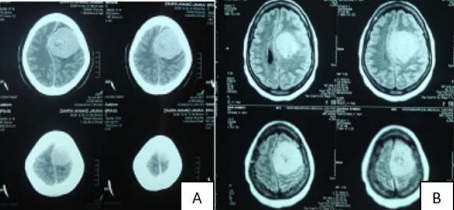

MRI and CT Brain showed lest sphenoid wing tumor.

Resected totally Histo. Grade 1 meningioma utilizing left pterional approach.

Image (A) preoperative MRI showing left temporal tumor in T1 axial cut with some sorrowing edema, Image (B) is operative view after total resection of the tumor

Image (C) one year postoperative axial MRI showing no evidence of the tumor, Image (D) is the patient after full recovery one year later.